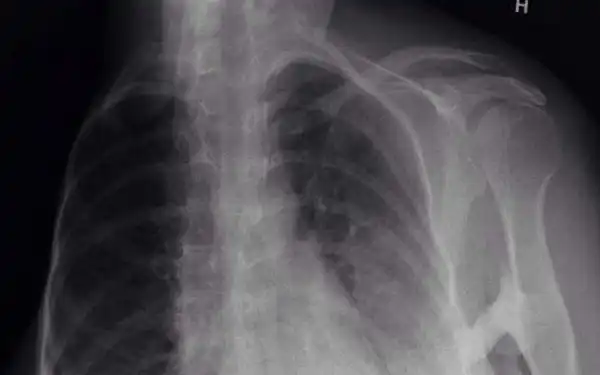

Оссифицирующая прогрессирующая фибродисплазия поразила около 800 человек по всему миру. В результате заболевания мышечная ткань превращается в кости. Эшли Курпил знает о всех "прелестях" фибродисплазии не по наслышке - она медленно, но верно превращается в статую. И лечения нет.

Женщина уже потеряла свою правую руку и подвижность в правой ноге. Но несмотря на это, она продолжает жить полноценной жизнью.